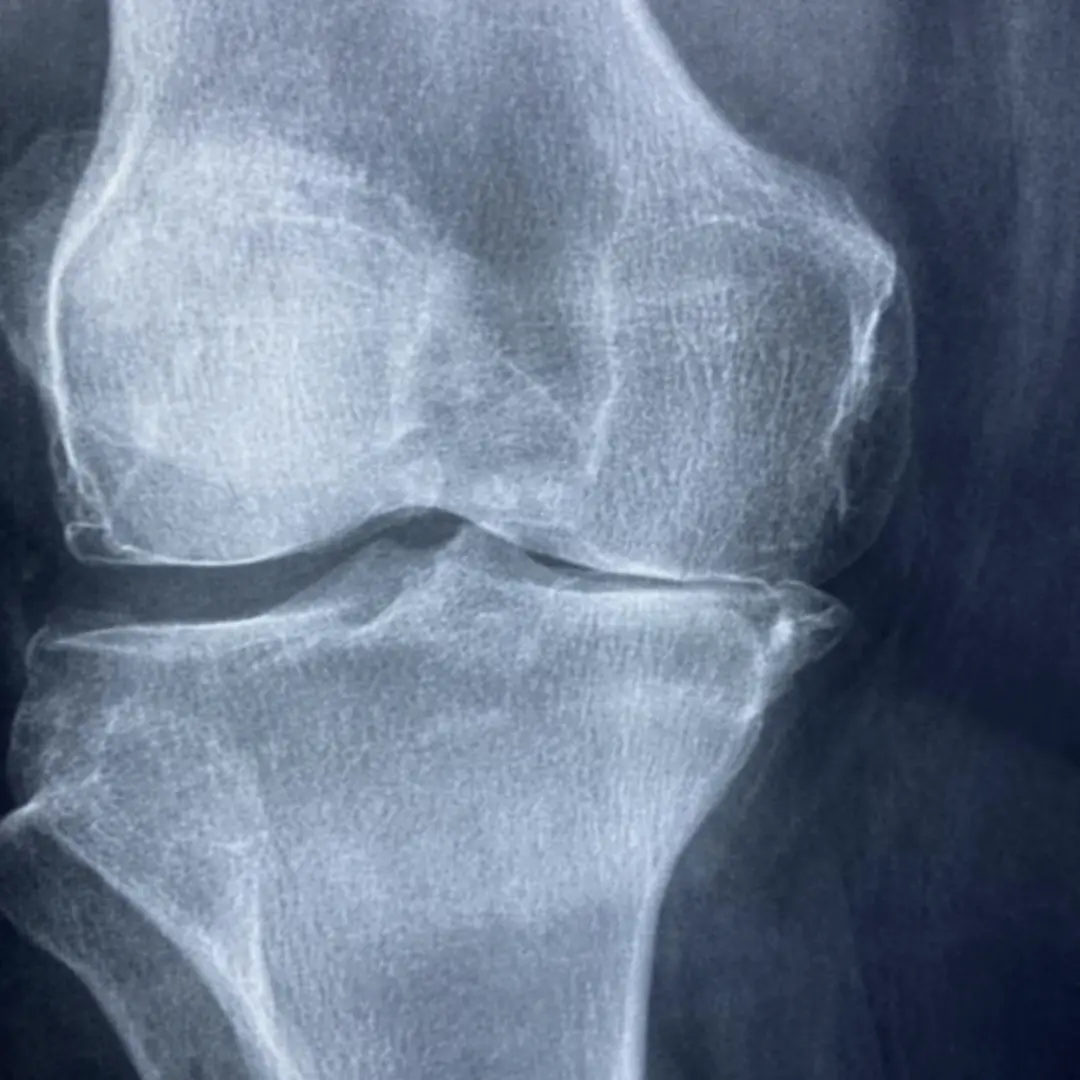

연골은 관절에서 뼈와 뼈가 직접 부딪히는 것을 막아주고, 충격을 흡수하며, 부드러운 움직임을 가능하게 하는 쿠션 역할을 합니다. 이 연골은 콘드로이틴과 함께 글루코사민을 통해 건강하게 유지될 수 있어요. 하지만 나이가 들거나, 과체중, 과도한 운동 등으로 인해 연골이 손상되거나 글루코사민 생성 능력이 떨어지면 연골이 닳아 없어지고 탄력을 잃게 됩니다. 이는 결국 관절 통증과 염증을 유발하는 퇴행성 관절염으로 이어질 수 있어요.